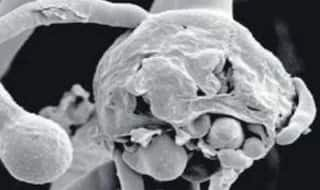

Black Fungus के बाद अब White Fungus मिलने से मचा हड़कंप, ज्यादा है खतरनाक, ऐसे करता है अटैक

Black Fungus के बाद अब बिहार की राजधानी पटना में White Fungus के चार मरीज मिलने से मचा है हड़कंप, यह फंगस ज्यादा खतरनाक है, जानिए कैसे करता है अटैक...